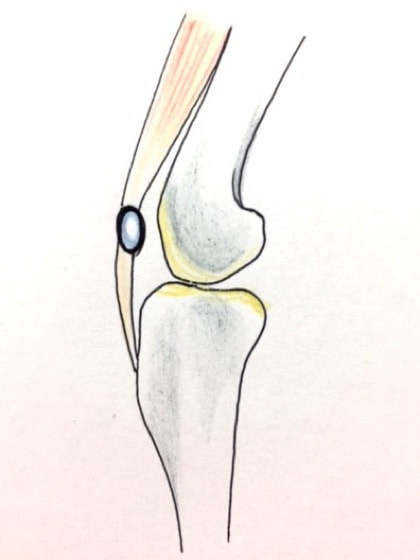

膝蓋骨が大腿骨遠位の滑車溝から内方または外方に転移する状態

本院では様々な整形外科手術に取り組んでおりますが、膝蓋骨脱臼の症例は、特に多く遭遇する疾患のひとつです。膝蓋骨脱臼は、その進行度に応じて4段階のグレード(グレードI~IV:Iが最も軽度、IVに近づくほど重度)に分類されます。当院ではグレードや症例にあわせて以下の4種類の手術法、

- 1.縫工筋、内側広筋の解放(medial release)

- 2.外側余剰関節包の切除と縫縮術(lateral tightening)

- 3.滑車溝深化術(deepening groove)

- 4.脛骨粗面移植術(tibial tuberosity transposition)

またはantirotational sutureなどを行い、安定した手術成績を残しています。しかし、最終グレードであるIVになり、膝関節の伸展が難しくなったり、骨格の変形が重度になると予後は不良です。状況により、治療のご説明をさせていただきます。